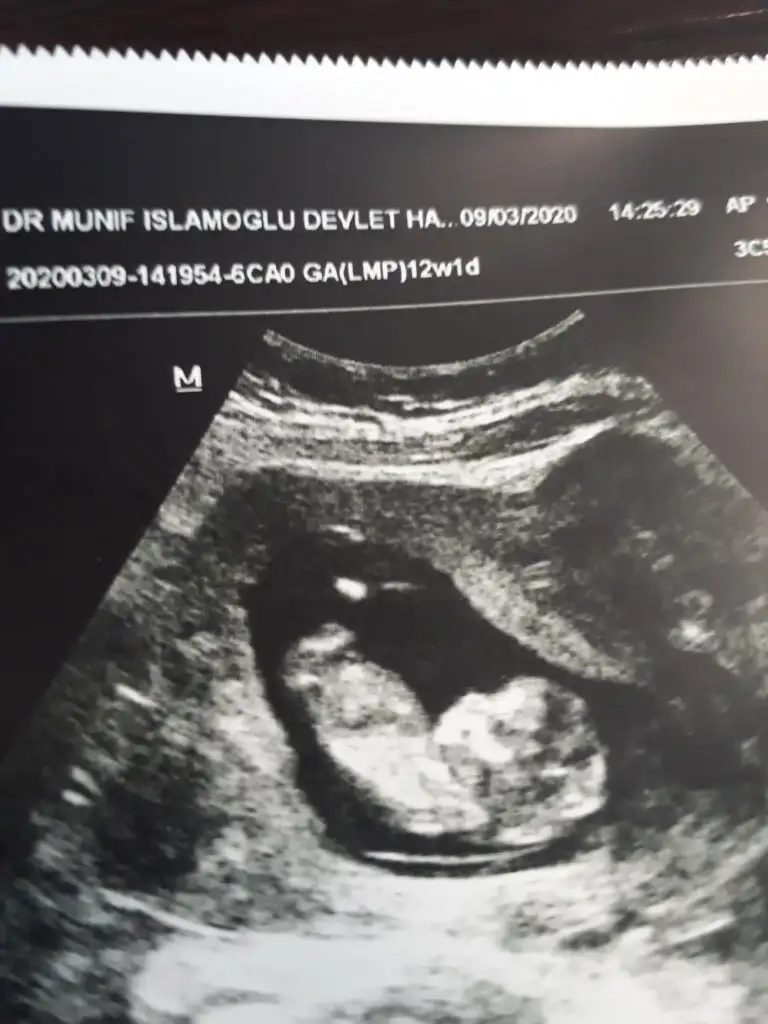

Kız sanki emin olamadım başka usgde paylaşınKızlar tahminde bulunabilirmisiniz ikiz bebekler 12 hafta 1 gunlikler

Bu kadar usg görüntüleri var malesefKız sanki emin olamadım başka usgde paylaşınsagdaki kız gibi digeri hiç görünmüyor

Tek yumurta ikizimi sanki ikiside kız tekrar usg olursa paylaşırsınız 13 haftada olurBu kadar usg görüntüleri var malesef